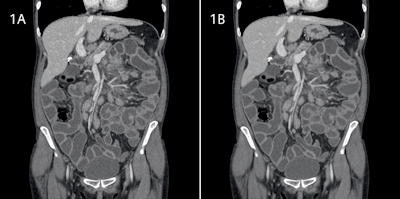

In the phantom, they found no significant difference between FBP and AIDR reconstructions in terms of spatial resolution assessment. Image noise was lower with AIDR than with FBP images with a mean reduction of 40%. The contrast-to-noise and the signal-to-noise ratios improved with AIDR. In patients, image noise was significantly lower with AIDR (31%) than with FBP, the researchers wrote. Signal-to-noise ratio was also greater with AIDR than with FBP.

"Our phantom study confirms that at an equivalent dose and compared to the traditional 3D-FBP algorithm used for volumetric reconstruction, AIDR iterative reconstruction generates a significant reduction of image noise," they noted. "Interestingly, the reduction level is equivalent, regardless of the initial quality of the original images. This means that AIDR reconstruction shows similar performances in terms of noise reduction for images acquired at normal dose than for noisy images acquired at low dose."

The finding that significant noise reduction does not alter spatial resolution is critical because "in regular clinical practice, several other methods already enable the reduction of image noise," the researchers noted. However, those techniques cause degradation in spatial resolution or an increase of the delivered dose. AIDR iterative reconstruction reduces noise without altering spatial resolution and without increasing the dose.